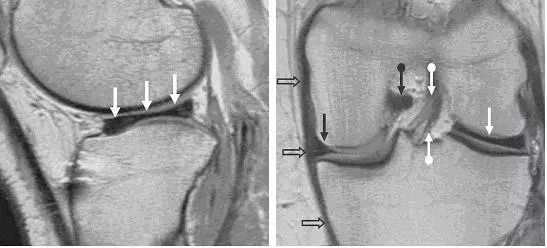

图 2 正常半月板

左图:外侧半月板,由于横截面面积一致,故在MRI 上可见外侧半月板前后角(纵向白色箭头)形状和大小较相似。上下腘肌半月板纤维束(黑色箭头)在外侧半月板后角处,形成裂孔,中间有腘肌腱(水平白色箭头)通过。右图:内侧半月板,可见后角(白色圆箭头),略大于前角(白色直箭头)